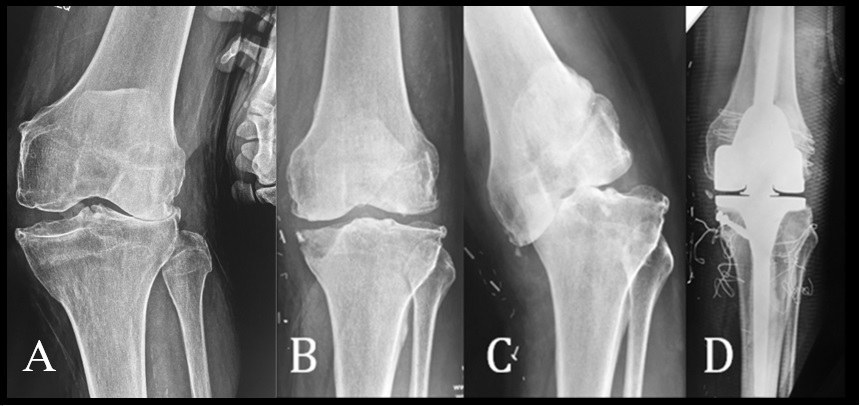

Se consideró el ligamento colateral suficiente, cuando en la maniobra de estrés no aumentaba la deformidad articular; atenuado cuando, por laxitud, el ligamento permitía el aumento de la deformidad, pero presentaba un tope mecánico claro (Figura 1a) e incompetente cuando aumentaba la deformidad como una bisagra, sin tope (Figura 2).

Se utilizó la clasificación de Ahlback para el genu varo artrósico, grado 1: pinzamiento del compartimento interno menor al 50 %, grado 2: pinzamiento interno completo, grado 3: déficit óseo tibial menor de 5 mm, grado 4: déficit óseo tibial mayor a 5 mm y grado 5: subluxación tibio femoral (Figura 1b, c).

Figura 1: A) Paciente con un genu valgo de 25º, que presenta LCM atenuado. B, C) Paciente con genu varo artrósico Grado 5 de Ahlback y gran defecto óseo del platillo medial. D) Radiografía post-op. Bisagra rotatoria e injerto óseo autólogo del platillo medial.

Se utilizó una prótesis estabilizada Plus® en 28 rodillas con una desalineación coronal con un promedio de 15,9°. De estas, 26 presentaron genu valgo artrósico (rango: 8° a 25°), 18 del grado 2, 3 de grado 3 y 5 de grado 4, de nuestra clasificación. Las dos rodillas restantes eran genu varo artrósico grado 4 de la clasificación de Ahlback. Se utilizaron prótesis constreñidas en 7 pacientes con genu valgo y una desalineación promedio de 23° (17° - 37°) (Tabla 2). Dos rodillas fueron clasificadas como grado 3 de la clasificación de genu valgo artrósico y 5 como gado 4. Empleamos bisagras rotatorias en 8 rodillas (Tabla 3), 3 en pacientes con genu varo artrósico (Figura 1) y una desalineación promedio de 16°, y 5 en pacientes con genu valgo artrósico (Figura 2) y una desalineación promedio de 24,6°. De los 5 pacientes con genu valgo, uno fue clasificado como grado 4 y los restantes como grado 5 de la clasificación de genu valgo artrósico. En un caso (genu valgo) se requirió la utilización de un suplemento metálico en el platillo tibial interno en un defecto óseo no contenido y en otro (genu varo) (Figura 1) se realizó un auto-injerto debido a la existencia de un defecto óseo tibial contenido. En todos los casos en los que se utilizó una prótesis constreñida o abisagrada se utilizaron vástagos femorales y tibiales.